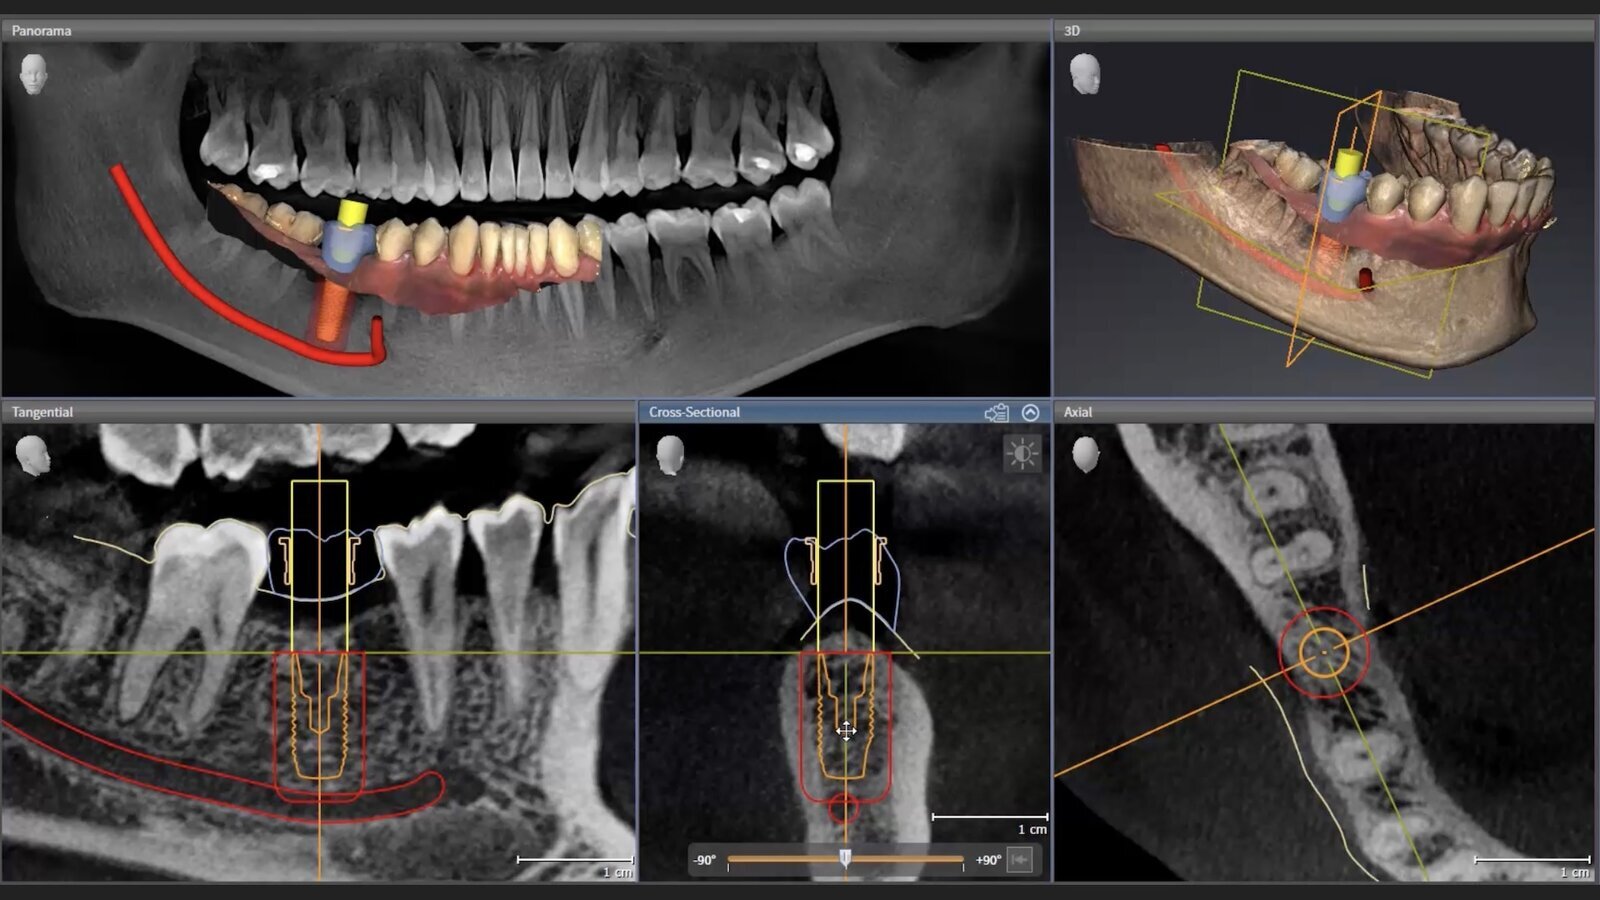

El software SICAT Implant permite al dentista controlar el flujo digital completo: desde el diagnóstico en 3D hasta la planificación digital de implantes, pasando por el diseño de guías quirúrgicas SICAT.

De este modo, los usuarios se benefician tanto de la excelente calidad de imagen de las unidades CBCT de W&H (Seethrough Max y Seethrough Flex), como de las herramientras para el diagnóstico y la planificación en 3D con SICAT Implant.

El software SICAT Implant ha sido diseñado para planificar la carga de implantes de forma no solo eficiente, sino también rápida e intuitiva. Gracias a su interfaz intuitiva, los usuarios sin experiencia previa en planificación digital de implantes pueden trabajar con precisión y minimizar el tiempo necesario.

El software incluye una extensa base de datos de implantes, actualizada continuamente, con más de 13.000 implantes, pilares y sistemas de los principales fabricantes. El enfoque automático de objetos, rotación de 360° alrededor del punto focal y el implante, avisos de colisión y la posibilidad de combinar cualquier dato DICOM CBCT con archivos STL, SSI y SIXD son solo algunas de las potentes funciones que ofrece el software.